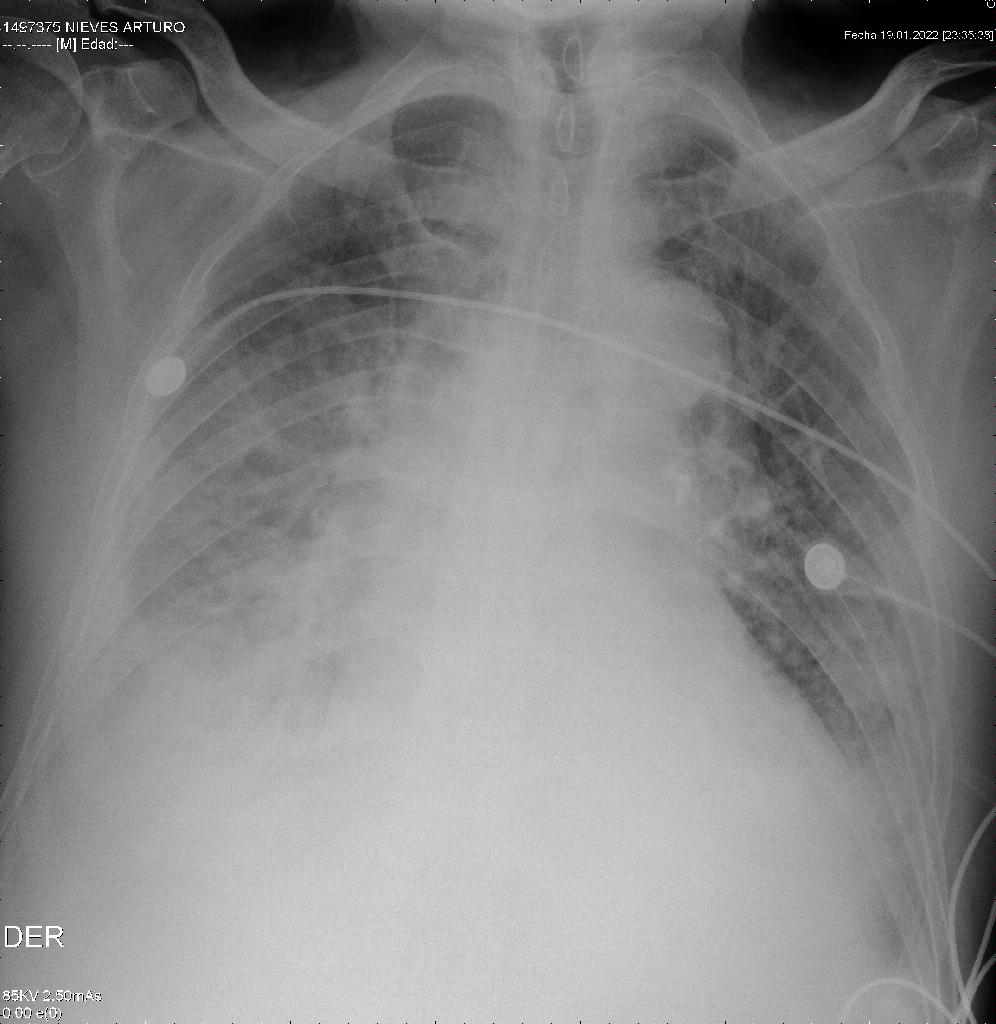

Se presenta el caso de un sujeto de sexo masculino de 83 años, con esquema de vacuna incompleta para COVID-19, sin vacunación para Influenza; adicionalmente con antecedente de falla cardiaca, insuficiencia aórtica severa, extabaquismo e hipertensión arterial. Ingresó al servicio de urgencias el día 13/01/23 por cuadro clínico de un (1) mes de evolución consistente en astenia, adinamia, disnea paroxística nocturna, ortopnea y edema en miembros inferiores. Se realizó diagnóstico de falla cardiaca congestiva descompensada, con edema agudo pulmonar (Figura 1). Se tomó ecocardiograma transtorácico (ECO TT) el 21/01/2023 con reporte de fracción de eyección del ventrículo izquierdo (FEVI) del 55%, válvula aórtica trivalva con esclerosis, insuficiencia severa, anillo 25 mm y válvula mitral con insuficiencia moderada a severa. Se descartó enfermedad coronaria obstructiva significativa por cateterismo cardíaco el 26/01/2023. Posteriormente el paciente fue evaluado en junta cardioquirúrgica donde fue ingresado a protocolo para implantación de válvula aórtica transcatéter (TAVI).

Radiografía de tórax de ingreso 13/01/2023

Figura 1. Radiografía de tórax de ingreso 13/01/2023